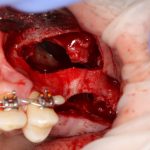

Установка имплантатов.

Напомню, что для этой работы я выбрал субкрестальные имплантаты Ankylos C/X. Они прекрасно сочетаются с любым методом остеопластики.

Я не планирую установку супраструктур или коронок, поэтому на уровень первичной стабильности можно положить болт. Даже наоборот — чем меньше крутящий момент при установке, тем лучше. Для имплантатов Ankylos и подобных им, это особенно важно. В общем, момент силы при установке — не более 10-15 Нсм.

Ремарка: имплантаты с предустановленными имплантодержателями хороши тем, что с ними легко контролировать позиционирование имплантатов. В случае с Ankylos С/Х - еще и крутящий момент. Имплантодержатель должен отсоединяться от имплантата с легким щелчком. Если его клинит, и тебе приходится прикладывать для этого усилия, то ты, однозначно, превысил момент силы во время установки имплантата. Следовательно, жди проблем.

Глянем на то, что получилось:

Осталось адаптировать костный блок (убрать острые края), проверить его фиксацию и, при необходимости, добавить винты. Десятисекундное дело.